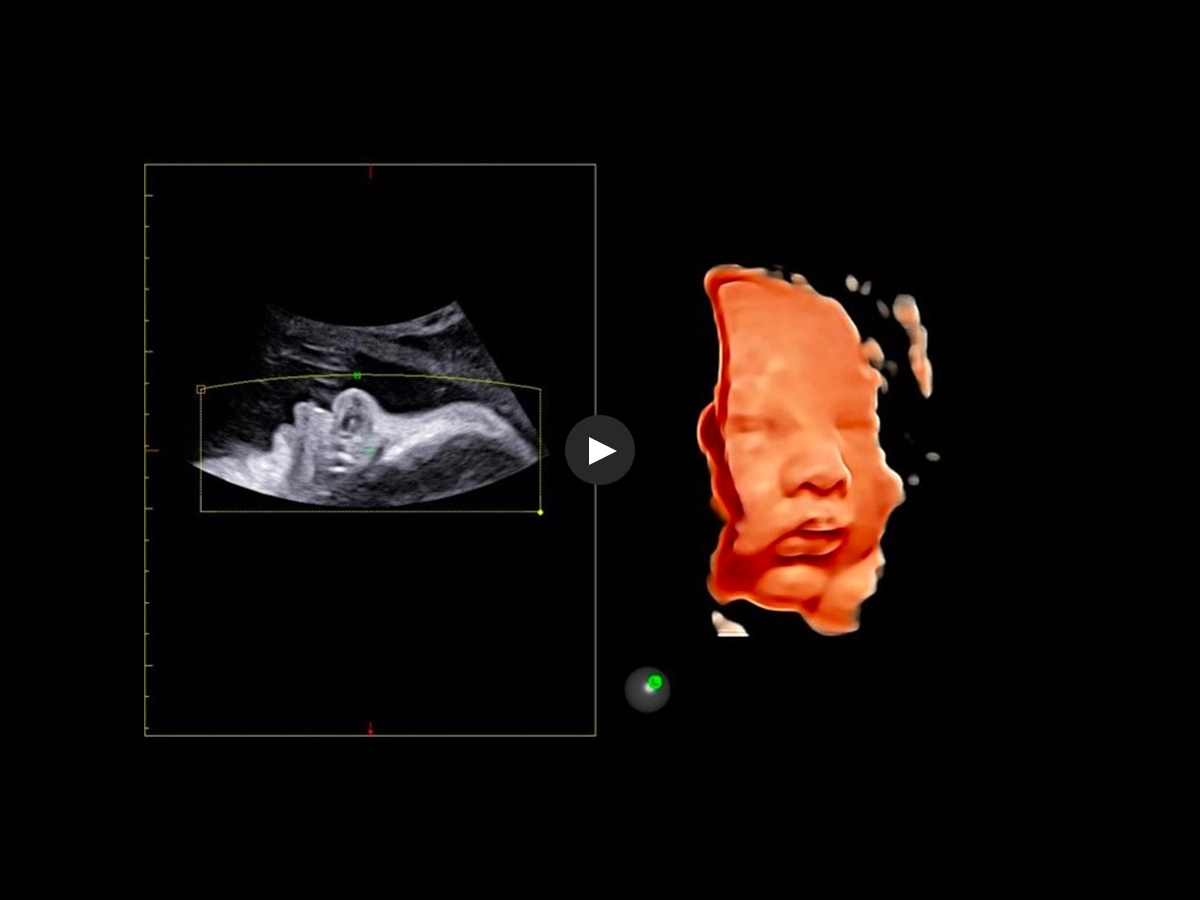

Esaote attaches great value to the quality of its 3D/4D imaging in order to provide very detailed picture of the baby’s features, depending on the stage of fetal development. Its environment is provided by different modalities, based on how the volume can be processed and rendered.

Esaote XLight technology, with its realistic diffusion effects and shadows, emphasizes the anatomical details of the fetus in baby face scanning; XGlass creates a transparency effect; bone rendering is ideal to study the baby’s spine; TSI (Thick Slice Imaging) is suitable for well-defined and confined structures, such as the corpus callosum; finally, XSTIC accurately evaluates the fetal heart.